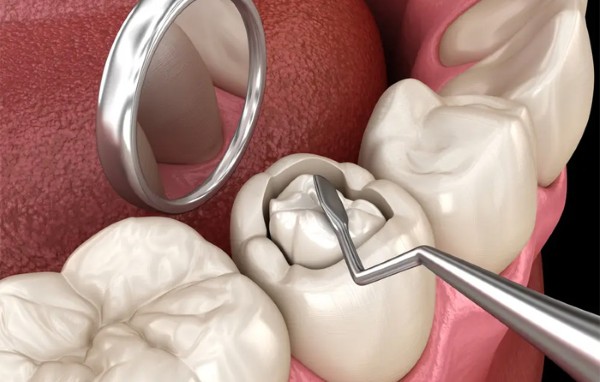

Trám răng thẩm mỹ cho lỗ sâu nhỏ và vừa

Đây là phương pháp can thiệp phổ biến và hiệu quả nhất cho các trường hợp sâu răng đen ở giai đoạn 1 và 2.

- Kỹ thuật thực hiện: Bác sĩ tiến hành nạo sạch các mô răng bị vi khuẩn tấn công (vết sâu đen) để ngăn chặn lây lan. sau đó, sử dụng vật liệu chuyên dụng như Composite hoặc GIC để lấp đầy lỗ hổng.

- Ưu điểm: Quá trình diễn ra nhanh chóng (chỉ từ 15 – 20 phút), không gây đau đớn và khôi phục hình dáng, màu sắc răng tự nhiên như ban đầu.

- Chi phí: Tại nha khoa, mức giá trám răng thẩm mỹ dao động từ 200.000đ – 500.000đ/răng tùy vào loại vật liệu và kích thước lỗ sâu.